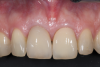

Fig 5. Preoperative clinical image of tooth No. 8 (1:1). A thin scalloped phenotype, prone to collapse upon removal of the tooth, was evident.

Figure 5

Fig 10. Oblique view of single-tooth implant No. 8 (1:1) treated with PET. Note the excellent retention of soft-tissue form around the restoration reflecting maintenance of the supporting buccal plate of bone.

Figure 10